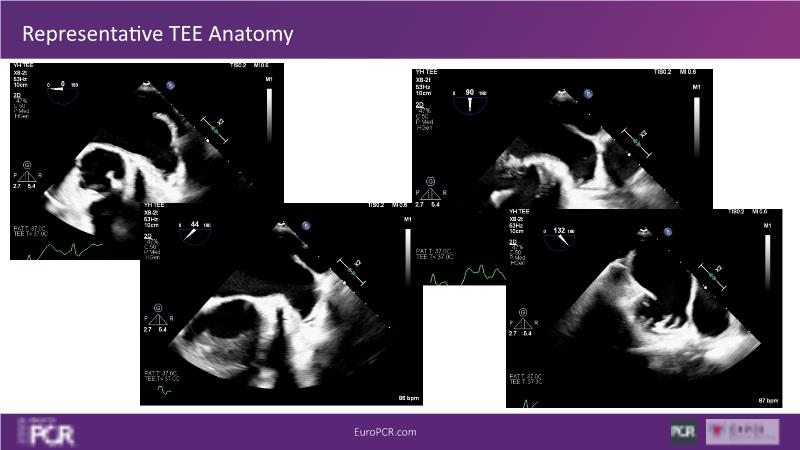

Explore this session to discover the latest innovations in interventional cardiology images, including the benefits of artificial intelligence and angio-CT in PCI/SHD procedures. Learn about Alphenix Evolve and the initial experiences with AI imaging in daily cathlab practice, alongside intraprocedural angio-CT guided LAAO, and engage in discussions on meaningful tools that can transform patient care.